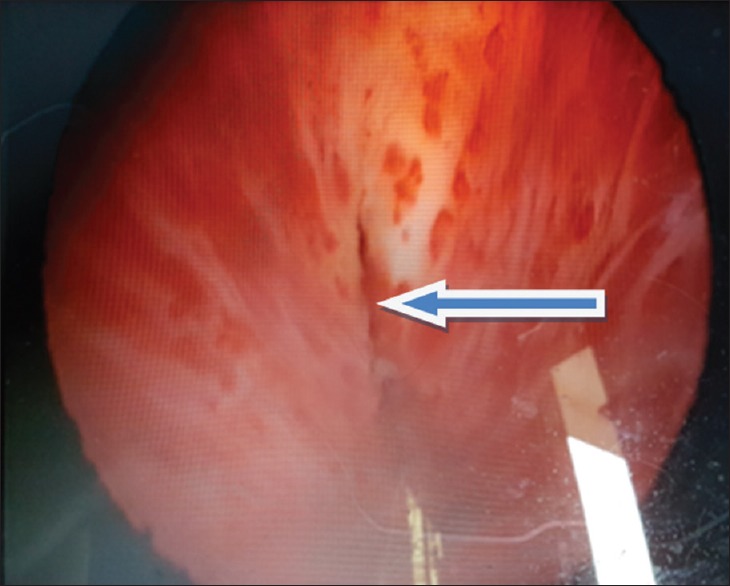

A 34-year-old civil servant presented to our facility, following a referral from a gynecologist who was also seeing the wife. The man presented with a history of anejaculation and the inability to impregnate his wife after 23 months of marriage. History, physical examination, and ancillary investigation led to a diagnosis of primary infertility secondary to posterior urethral valve which was subsequently ablated. Three weeks after ablation, he started ejaculating, and 2 months later, the wife became pregnant.

Abstract Image